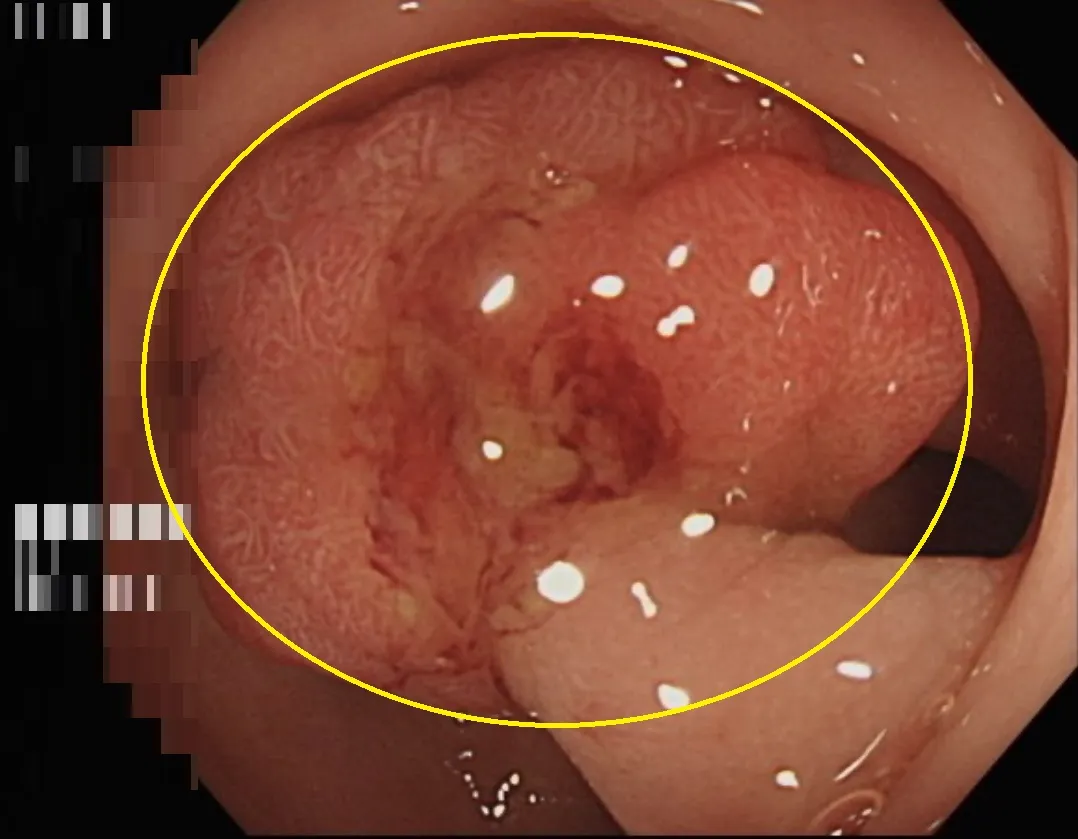

大腸鏡檢查影像報告瘜肉(黃圈處)屬於原位癌,幸好僅存在於表層黏膜尚未擴散。

台中一名50歲林姓婦女在糞便潛血篩檢中呈現陽性反應,隨即至長安醫院肝膽腸胃科門診接受檢查。透過大腸內視鏡發現在乙狀結腸處有一個1.5公分大小的瘜肉。切片報告顯示為大腸原位癌,所幸及時切除乾淨,沒轉移到其它器官的風險。林女士直呼超幸運,還好有來做篩檢,一定會照醫囑定期回診追蹤。

許鈺銓醫師表示,這位病患因為糞便潛血篩檢陽性反應前來就診,詢問病史及理學檢查並無其他異狀。但陽性反應意味著大腸內可能存在息肉或腫瘤,為確保安全,安排了大腸內視鏡檢查,最終發現在乙狀結腸處有一個1.5公分大小的瘜肉。當場進行了瘜肉切除手術,並安排後續回診。

兩週後,病理報告確認該瘜肉為黏膜內腺癌,俗稱大腸原位癌。許醫師解釋,原位癌是最早期的癌症,此時癌細胞僅存在於表層黏膜,尚未侵入其他組織。只要及早發現並切除,患者就能避免後續的開刀、化療等復雜治療。好消息是切除後檢查顯示瘜肉邊緣無殘存癌細胞,表示已清除乾淨,經過解釋及衛教,病患六個月後再接受大腸內視鏡追蹤即可。